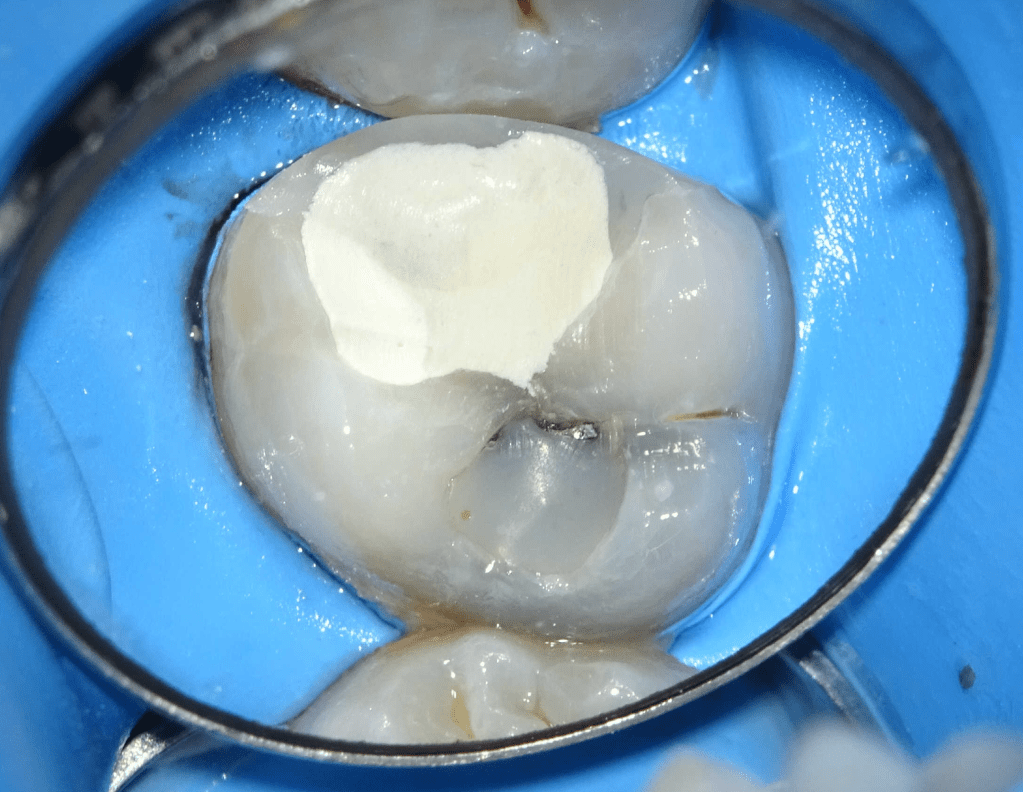

Reconstrucción preendodóntica

Reco pared vesticular